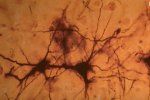

Le neurone

Un neurone, ou cellule nerveuse, est une cellule excitable constituant l'unité fonctionnelle de base du système nerveux. Nous en avons 100 milliards.

Cellule du système nerveux constituée d'un corps cellulaire (renfermant le noyau), de dendrites (parties réceptrices courtes et ramifiées) et, d'un ou plusieurs axones (si le nerf est moteur) ou d'un dendrone (sorte de longue dendrite, si le nerf est sensoriel).

Les ramifications du neurone permettent la propagation de l'influx ou message nerveux. Ce message est un signal de nature électrique qui se propage le long du neurone. D'un neurone à l'autre, le message se transmet dans des zones de contact spécialisées appelées synapses.